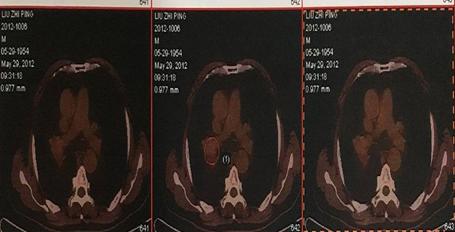

患者刘某某,男,65岁, 13年前因咳嗽、咳痰带血半年就诊,胸部CT示右上肺占位,支气管镜示右上叶前段支气管远端狭窄,活检病理:中低分化鳞癌。诊断:右上肺中低分化鳞癌,T4N1M0,IIIB期。